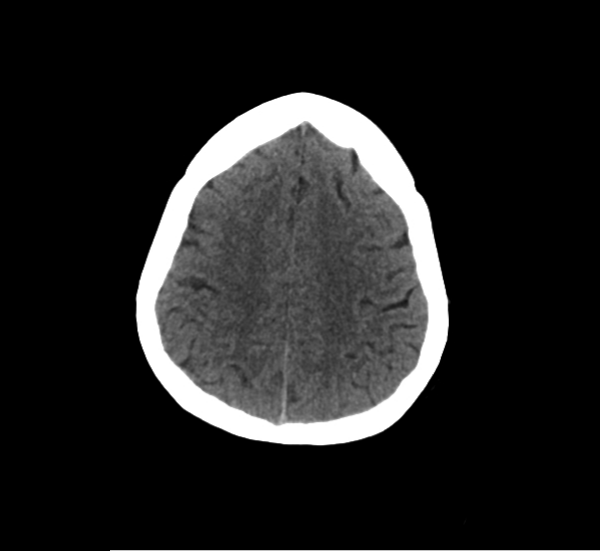

CT Brain Anatomy